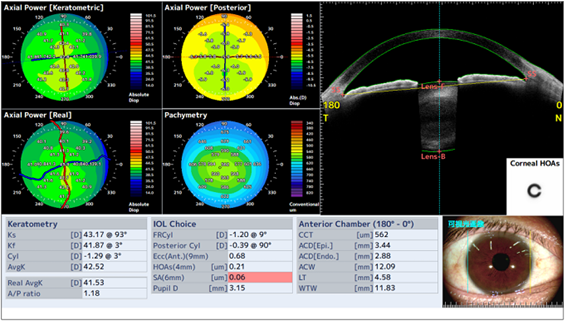

白内障術前検査にて角膜の不正乱視の有無をチェックし、多焦点眼内レンズに適用があるかどうかの情報を提供します。

角膜前面形状に加えて角膜後面形状も実測値を使った角膜全体乱視度数から患者さんに適したトーリック眼内レンズの円柱度数情報を提供します。